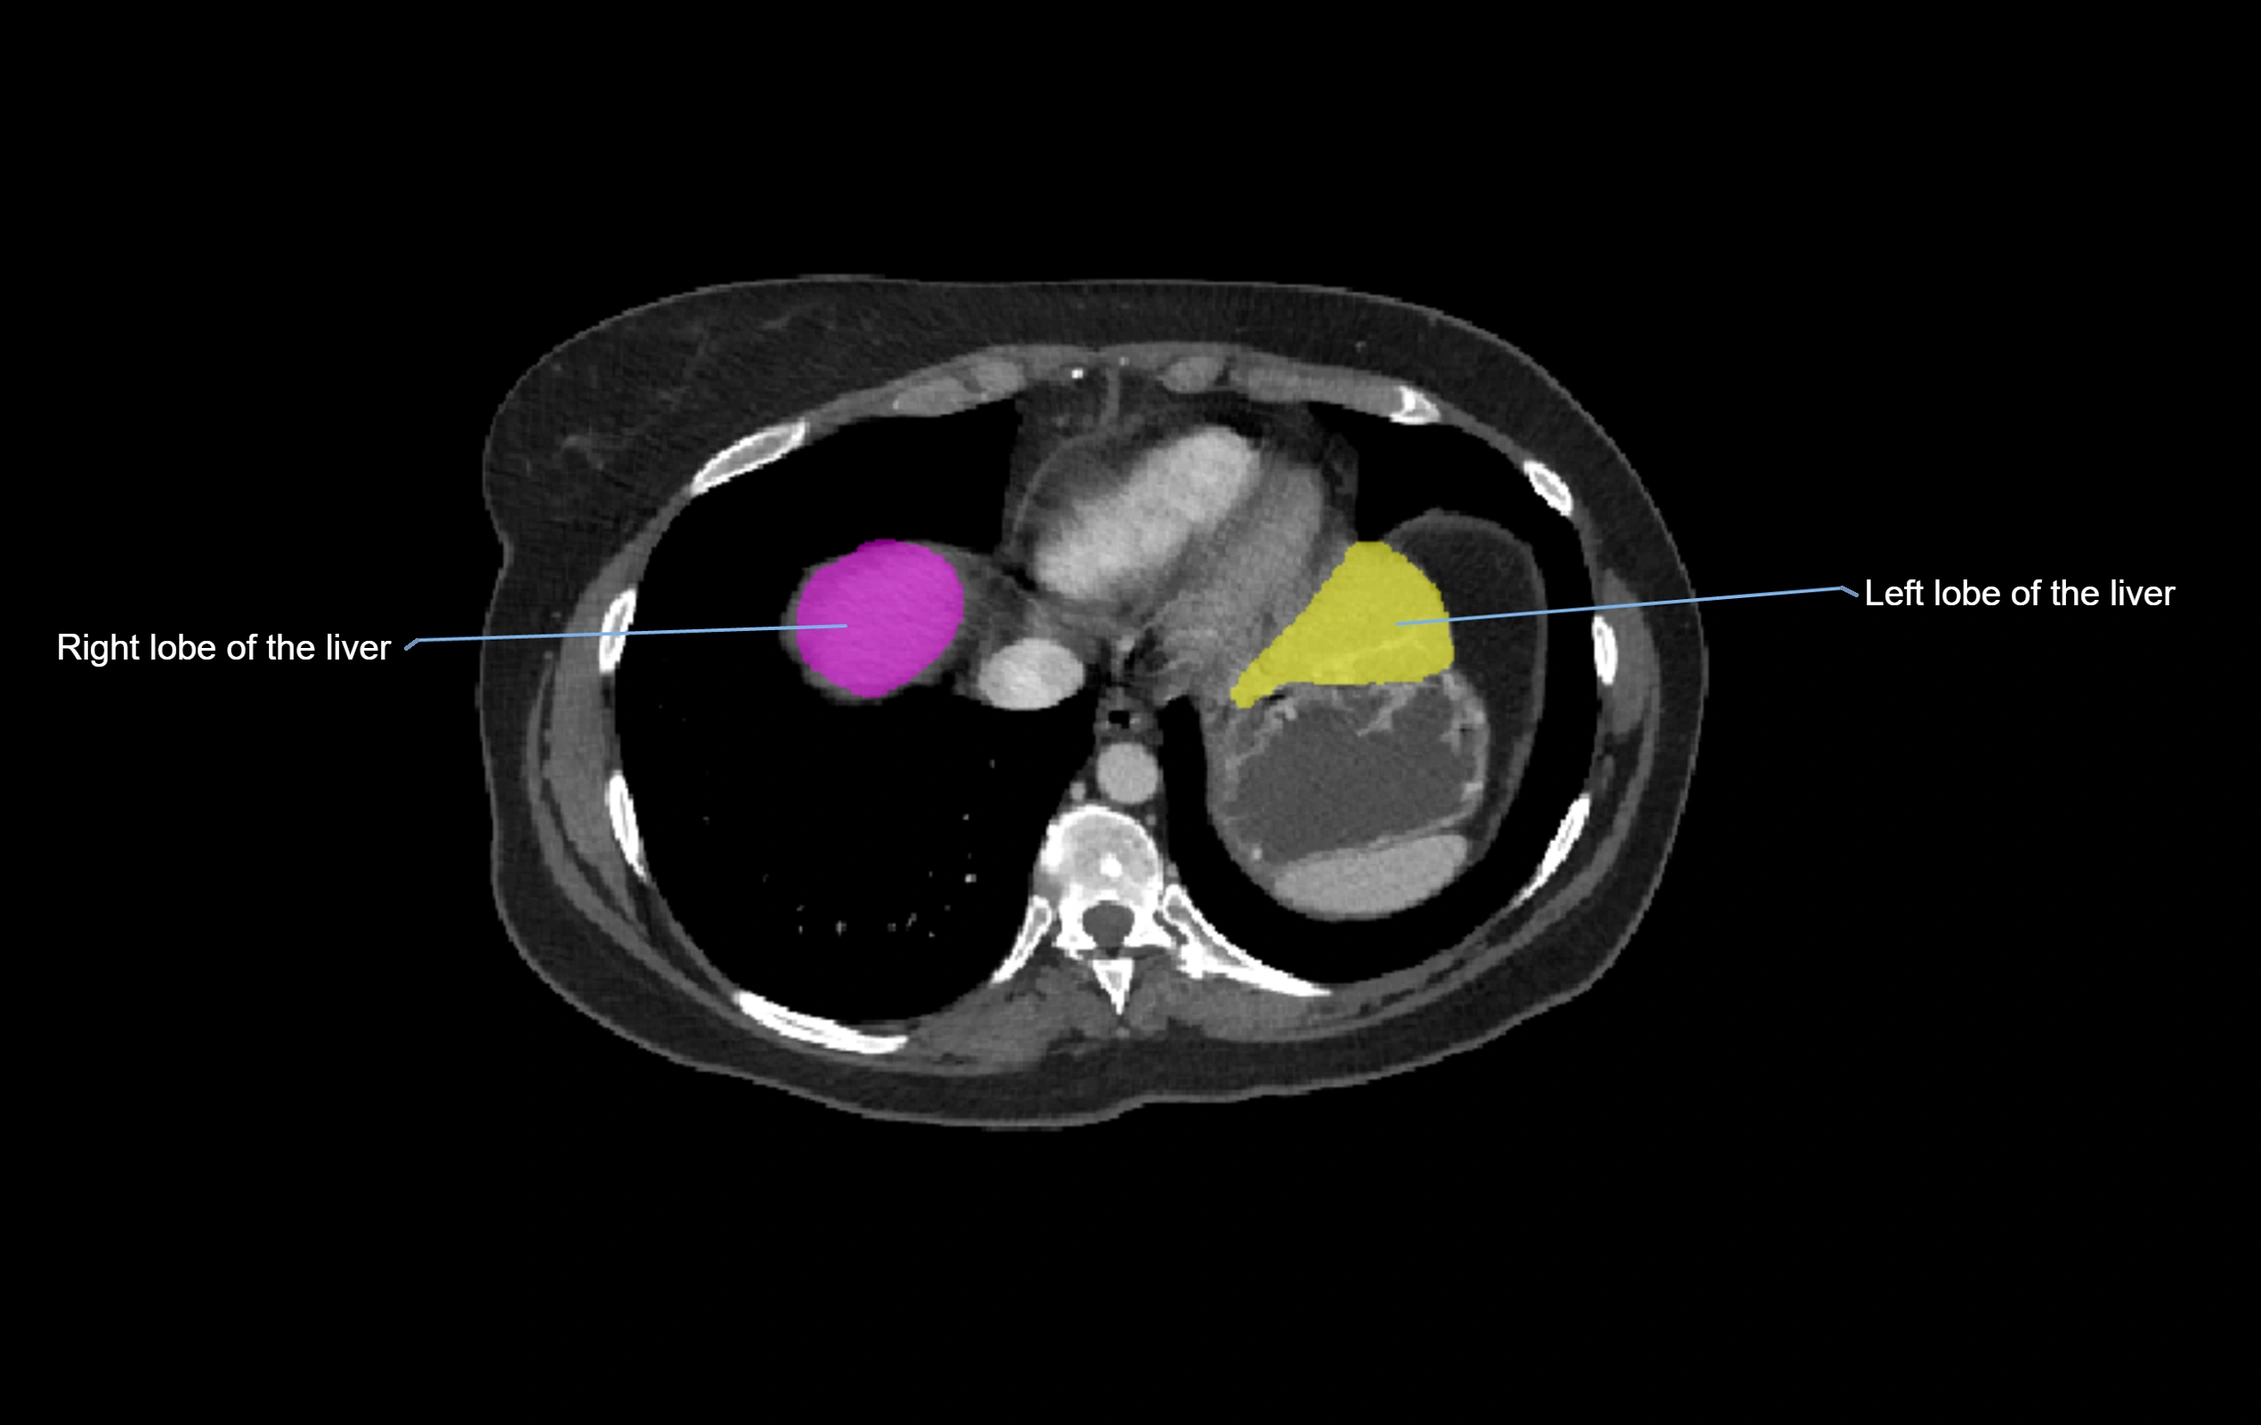

CT Image

image